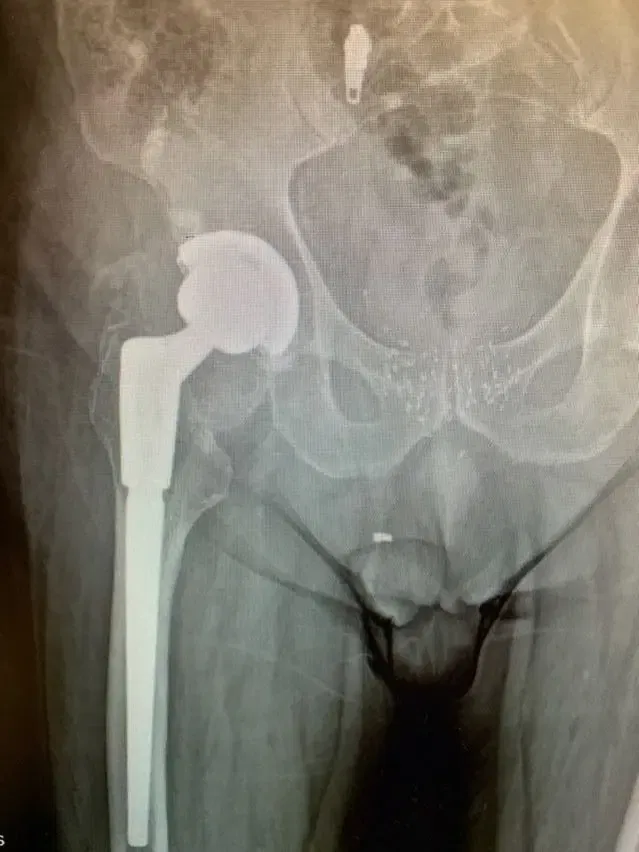

El Sr. JF es un caballero de 83 años que se había sometido previamente a un reemplazo total de cadera en otra institución aproximadamente 13 años antes de ser remitido a mí. Al principio se recuperó bien de la intervención y había estado asintomático durante gran...